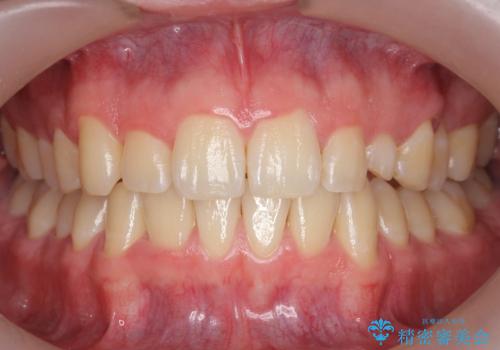

[ 前歯のねじれ・がたつき ] マウスピース矯正

![[ 前歯のねじれ・がたつき ] マウスピース矯正の症例 治療前](https://seimitsushinbi.jp/wp/wp-content/uploads/2024/02/4007c6479f6bce11863dcdd32ed5e39b-500x350.jpg?v=1708502552)

![[ 前歯のねじれ・がたつき ] マウスピース矯正の症例 治療後](https://seimitsushinbi.jp/wp/wp-content/uploads/2024/02/e7a01485e4f4dd0da04705fde4cc34cc-500x350.jpg?v=1708502585)

インビザライン モニター治療 前歯のねじれをまっすぐに